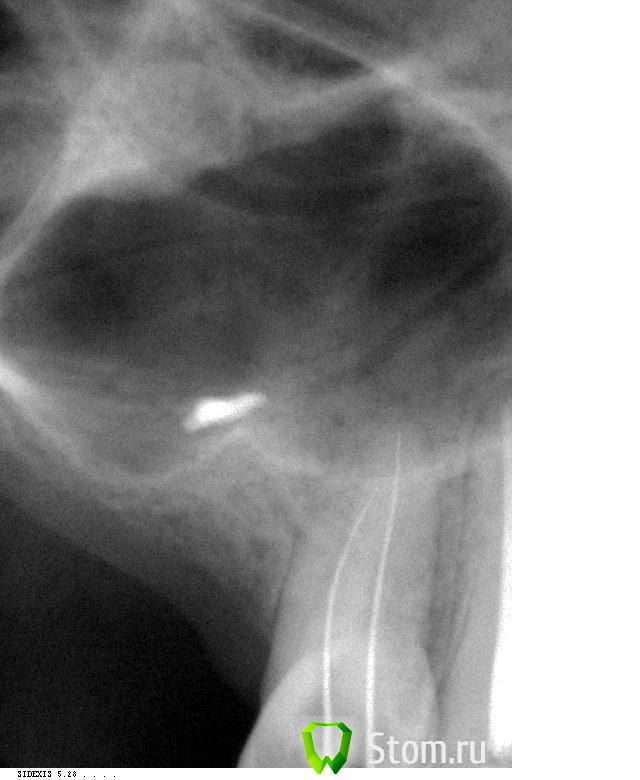

Catherine Опубликовано 5 марта, 2012 Автор Поделиться Опубликовано 5 марта, 2012 Собственно, вот снимки с иглами. Ссылка на комментарий

д-р Вит Опубликовано 5 марта, 2012 Поделиться Опубликовано 5 марта, 2012 хорошие снимки.дальше инструментами идти не стоит(имхо),помойте хлоркой разогретой с уз хорошенечко,при паковке получите картинку апекса. Ссылка на комментарий